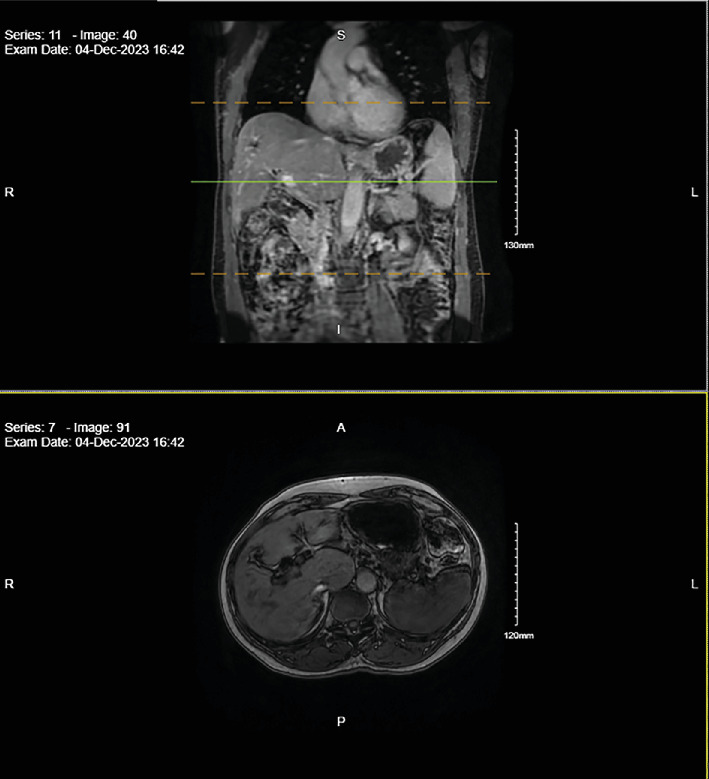

转移性壶腹癌(AC)几乎总是预后不良。我们报告了一个值得注意的病例,一位69岁的男性IV期胰胆型AC患者在经过45个月的姑息性改良FOLFIRINOX化疗(5-氟尿嘧啶、奥沙利铂、亚叶酸钙、伊立替康)后完全缓解。这一意想不到的结果挑战了对晚期AC自然史的传统理解。此外,分子分析显示,在编码各种脱氧核糖核酸(DNA)修复途径的酶的POLD1和RAD50基因中,存在致病性PALB2突变以及未知意义的变异。这些发现提出了它们对治疗反应和预后的潜在影响的问题。该病例强调需要进一步研究分子改变和个性化方法在晚期AC治疗中的作用。

Metastatic ampullary carcinoma (AC) almost always carries a poor prognosis. We present a remarkable case of a 69-year-old male with Stage IV pancreaticobiliary-type AC who achieved a complete remission after 45 months of palliative modified FOLFIRINOX chemotherapy (5-fluorouracil, oxaliplatin, leucovorin, irinotecan). This unexpected outcome challenges the conventional understanding of the natural history of advanced AC. Furthermore, molecular analysis revealed a pathogenic PALB2 mutation, along with variants of unknown significance in the POLD1 and RAD50 genes, coding for enzymes involved in various deoxyribonucleic acid (DNA) repair pathways. These findings raise questions about their potential influence on treatment response and prognosis. This case underscores the need for further investigation into the role of molecular alterations and personalized approaches in managing advanced AC.